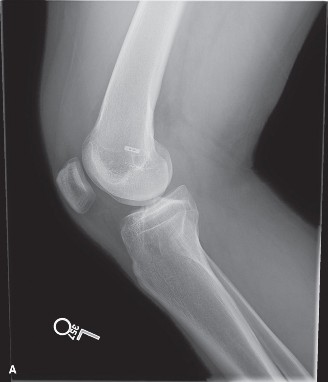

The correct answer is (A). An MRI of a quadriceps tendon rupture is demonstrated in Figure 9–3. The inability to extend the leg against gravity is most consistent with an injury to the extensor mechanism. The absence of tenderness on palpation and pain with passive motion makes a patella fracture unlikely. A transient patella dislocation can result in swelling but does not prevent a straight-leg raise. Placing the patient in the lateral decubitus position eliminates gravity as a resisting force.

Figure 9–3